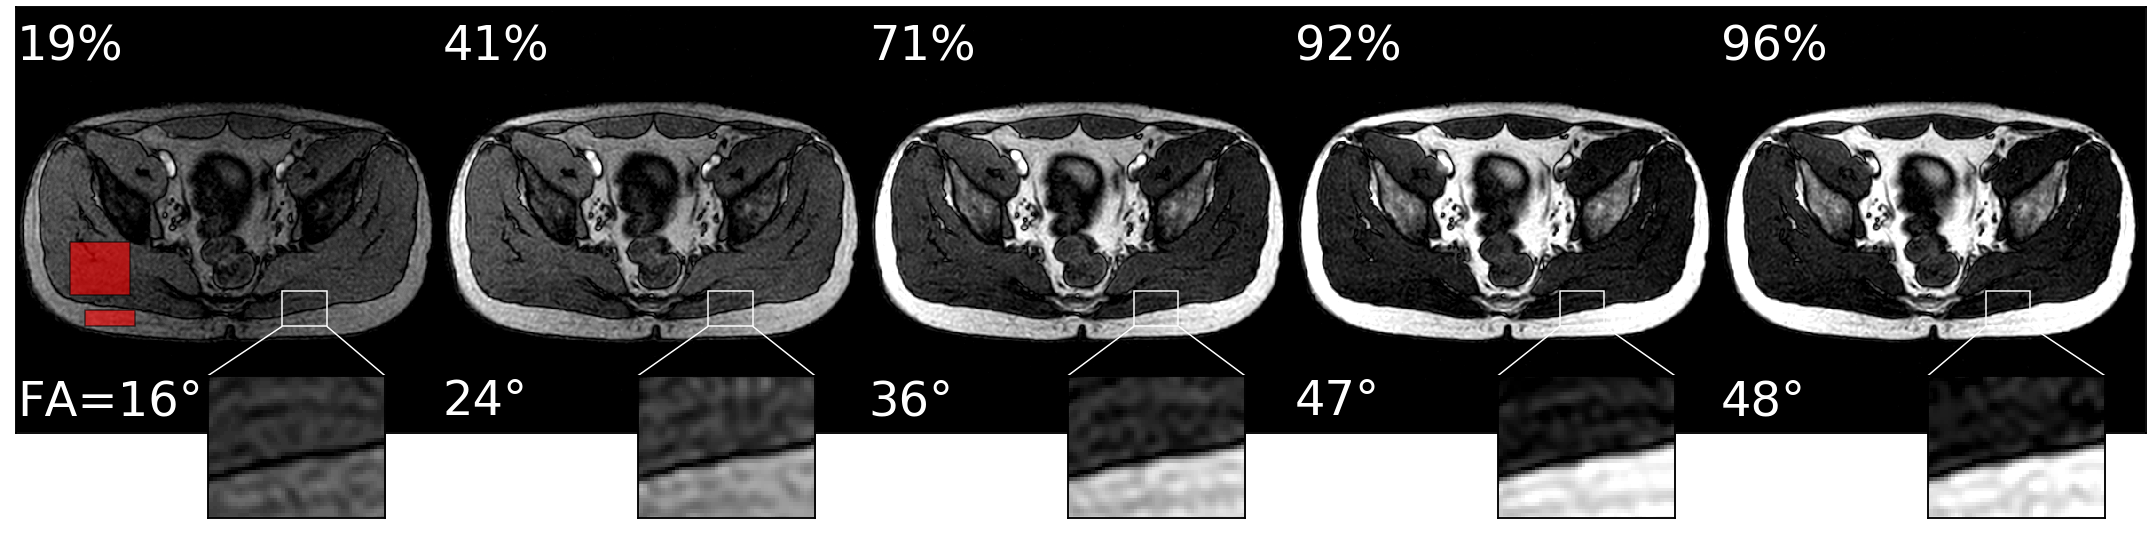

Figure 5: In-vivo results. The CNR was maximized between the red rectangles in an online in-vivo setting. The top number is the relative CNR compared to the optimal CNR, as empirically determined at 50 degrees. The bottom number shows the flip angle, while the zoomed region highlights the contrast. The first scan is the starting image, and within four steps, the model reaches 96% of the optimal CNR. The acquisition time per image was approximately two seconds, while data communication and model inference took about 1 second.